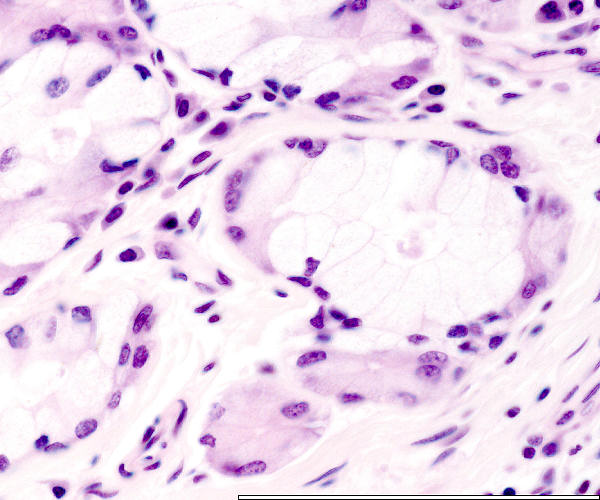

Pharyngeal tube: glands

Lumen

Mucinous secretory unit

Serous secretory unit

Serous demilune